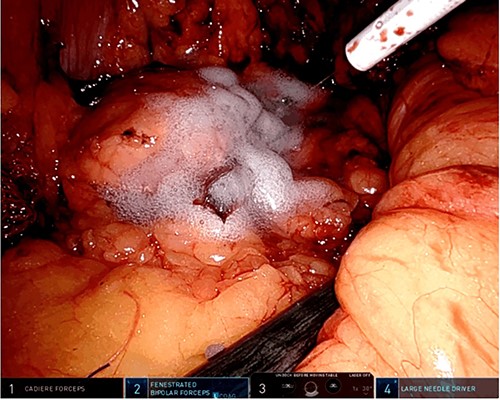

A robotic redo distal pancreatectomy was performed. Adhesions from the previous operation were taken down and the pancreatic stump was dissected. Samples of lymphatic tissue were sent for permanent pathology. An intraoperative ultrasound scan was done to localize the tumor and rule out concomitant lesions. A 2-cm nodule was found in the pancreatic stump (Fig. 3). With precise dissection, the gland was mobilized, reaching the confluence of the splenic and the portal vein. Afterward, the pancreatic stump was resected using a linear stapler (Fig. 4A and B). Once hemostasis was obtained, fibrin glue was applied to the section line and two drains were left close to the stump (Fig. 5). The patient was discharged on postoperative day 7. She developed a pancreatic biochemical leak that was managed conservatively. The histopathology analysis showed a grade 2, 1.3 cm well-differentiated neuroendocrine tumor with a low mitotic rate and Ki 67 index of 3%. After 16 months of follow-up, there was no evidence of recurrence.

Intraoperative picture showing the pancreatic resection with a linear stapler (A) and the pancreatic stump with the stapler reinforcements in the resection line (B).